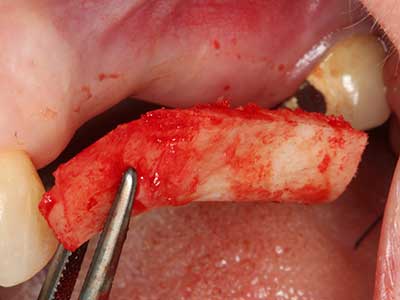

I trapianti autologhi dell'osso si eseguono in forma di blocchi, strati e anelli, anche in combinazione con materiali di riempimento tipo microframmenti. Se il sito dell'impianto viene preparato contemporaneamente all'accrescimento, diversi sistemi di filtraggio dell'osso si sono rivelati efficaci per la raccolta dei microframmenti ossei risultanti. Come metodo alternativo, il sito dell'impianto può essere preparato utilizzando un dispositivo a bassa velocità senza irrigazione. Senza l'inserimento di un impianto, è possibile raccogliere i microframmenti ossei dalla periferia mediante bisturi affilati per tessuto osseo. Ciò può essere eseguito anche con la piezochirurgia mediante appositi raccordi che raccolgono microframmenti ossei di qualità più elevata rispetto a quelli raccolti con trapani rotondi, come è stato confermato in uno studio comparativo dei due metodi (Chiriac, Herten et al. 2005).

La piezochirurgia presenta altri vantaggi per quanto riguarda la raccolta di blocchi ossei. Oltre all'elevata precisione dell'osteotomia appena descritta, l'utilizzo di puntine per sega molto sottili permette di minimizzare in maniera significativa la perdita di materiale. È molto probabile che si verifichi una maggiore perdita di materiale durante la raccolta utilizzando puntine di strumenti più spessi, in particolare delle frese Lindemann (Lakshmiganthan, Gokulanathan et al. 2012). La separazione basale, necessaria in particolare per i trapianti di blocchi nella zona retromolare, viene semplificata grazie a seghe specificatamente progettate di forma rettangolare; di conseguenza la piezochirurgia è considerata una procedura precisa, semplice e sicura per la raccolta di blocchi di osso nella zona retromolare (Happe 2007) (figg. 1-12).